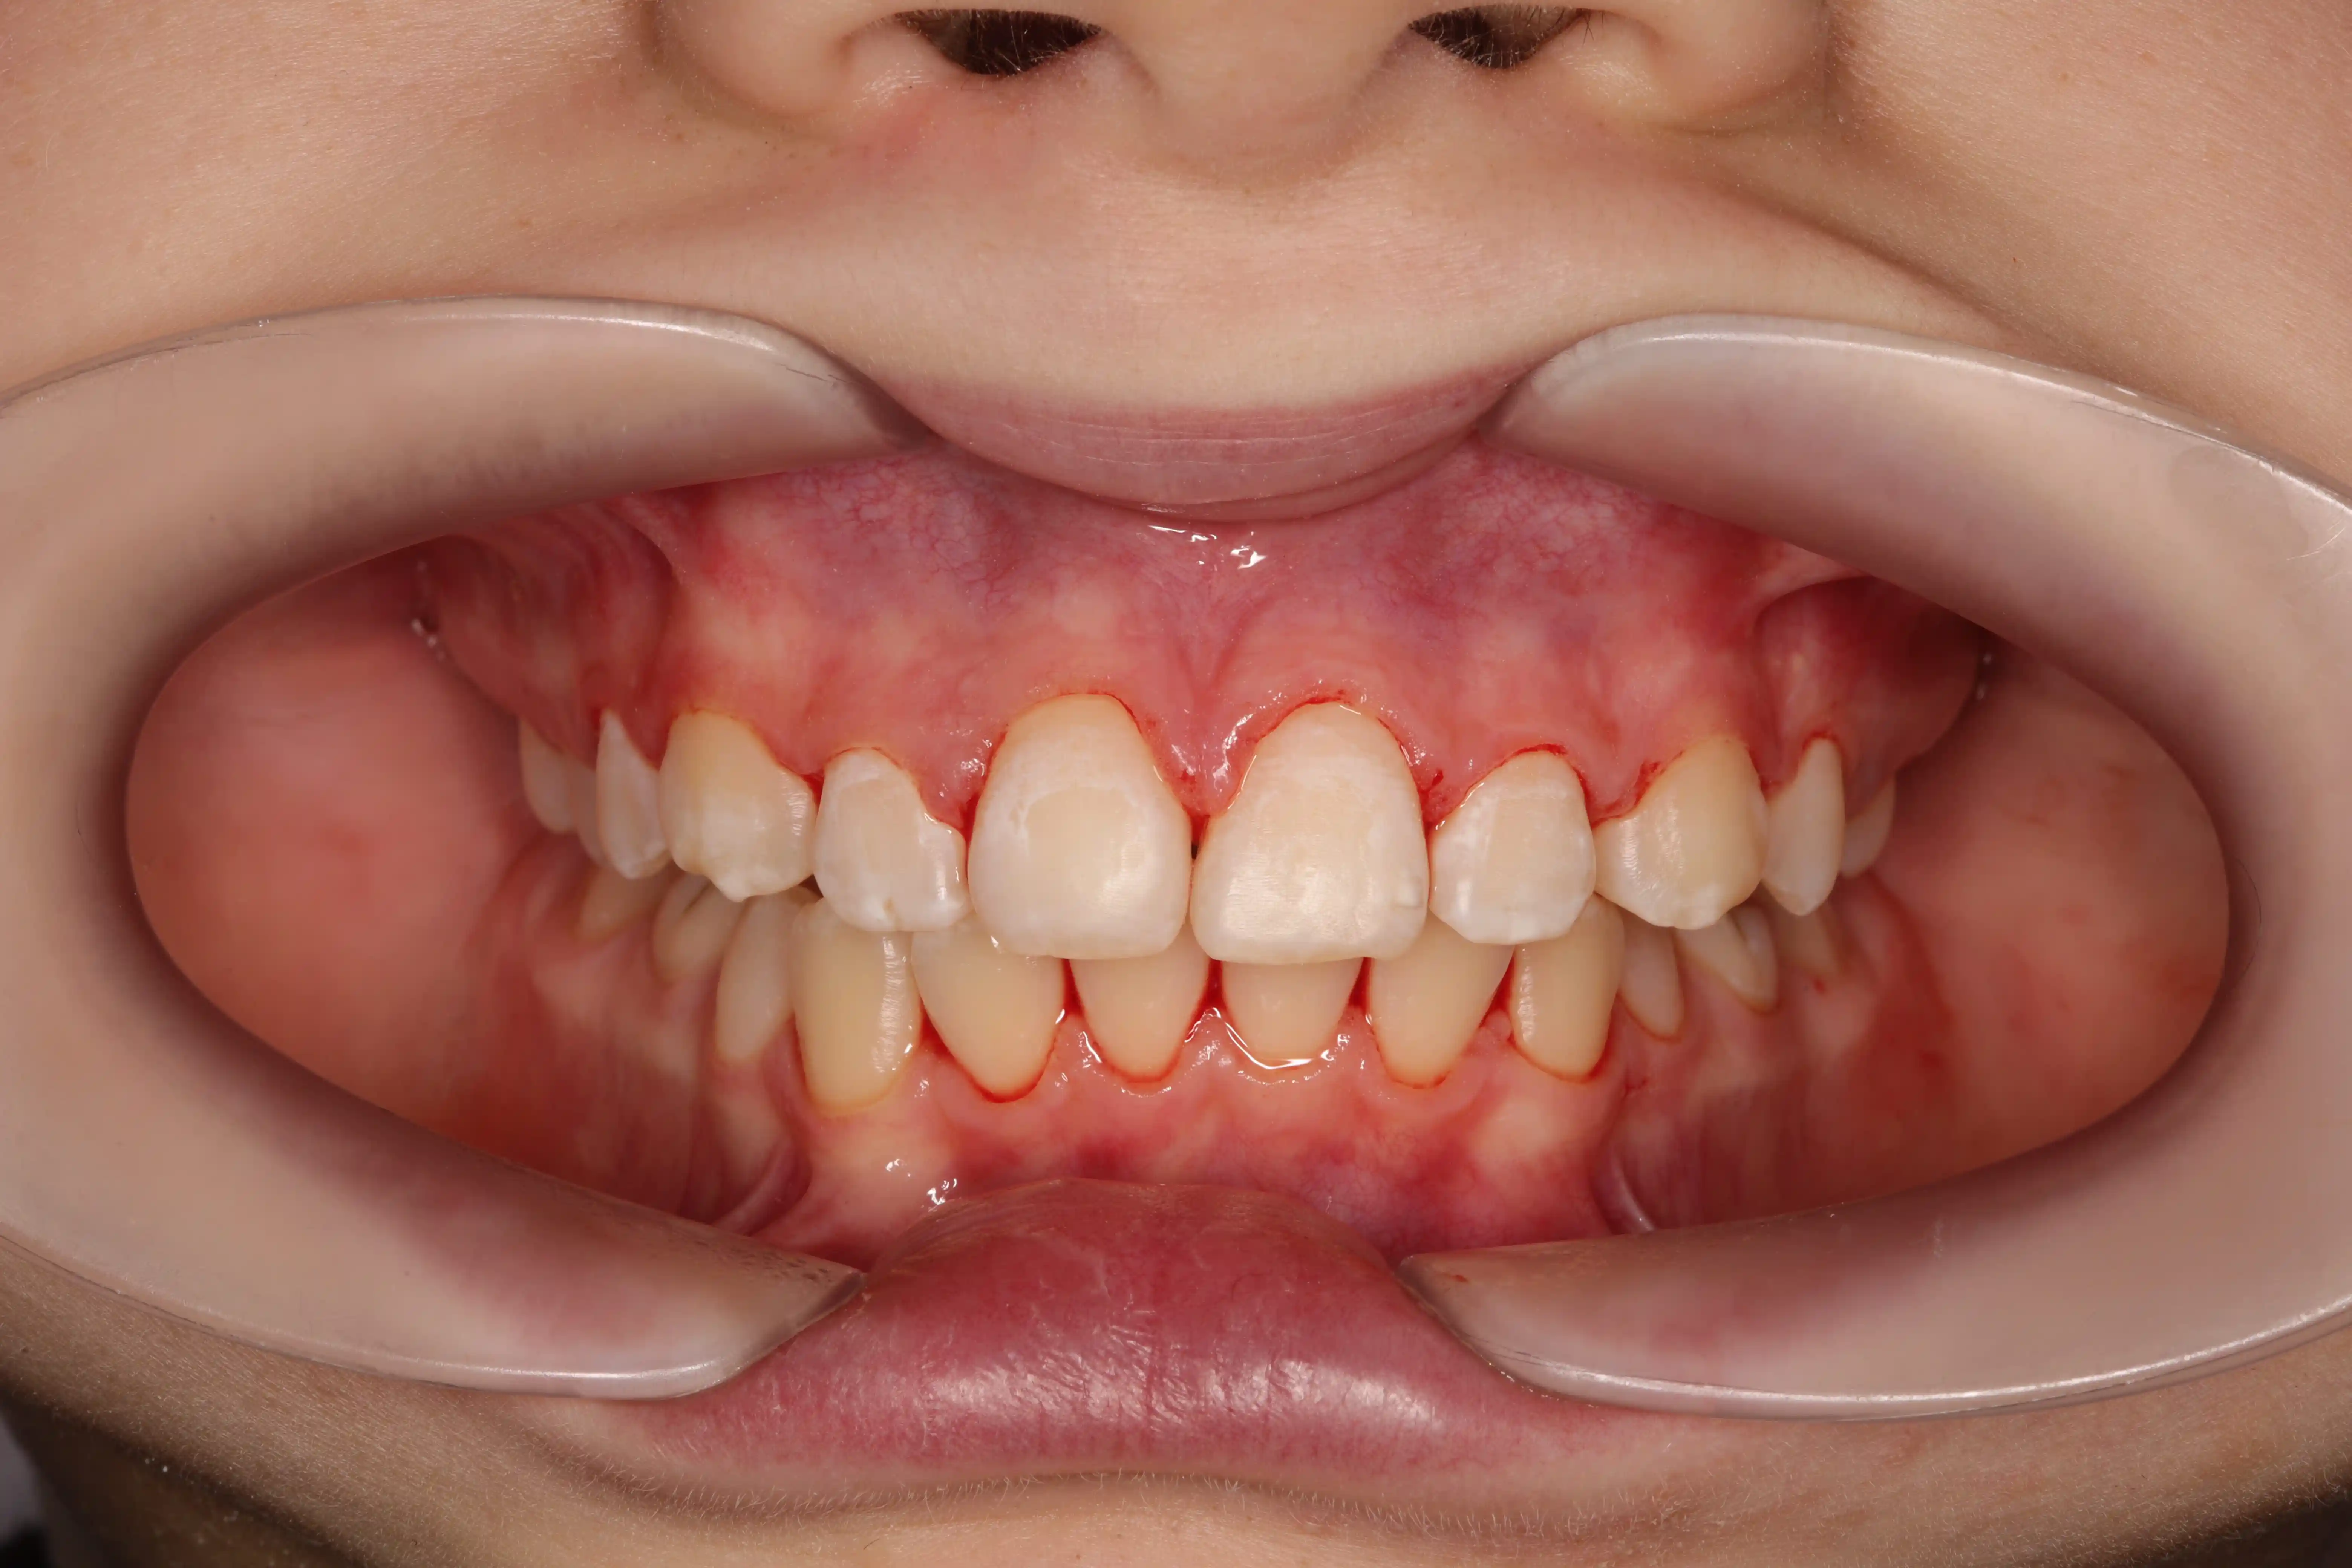

після

Результат - відновлений баланс у фронтальній ділянці, правильне положення зубів і передумови для гармонійного розвитку прикусу